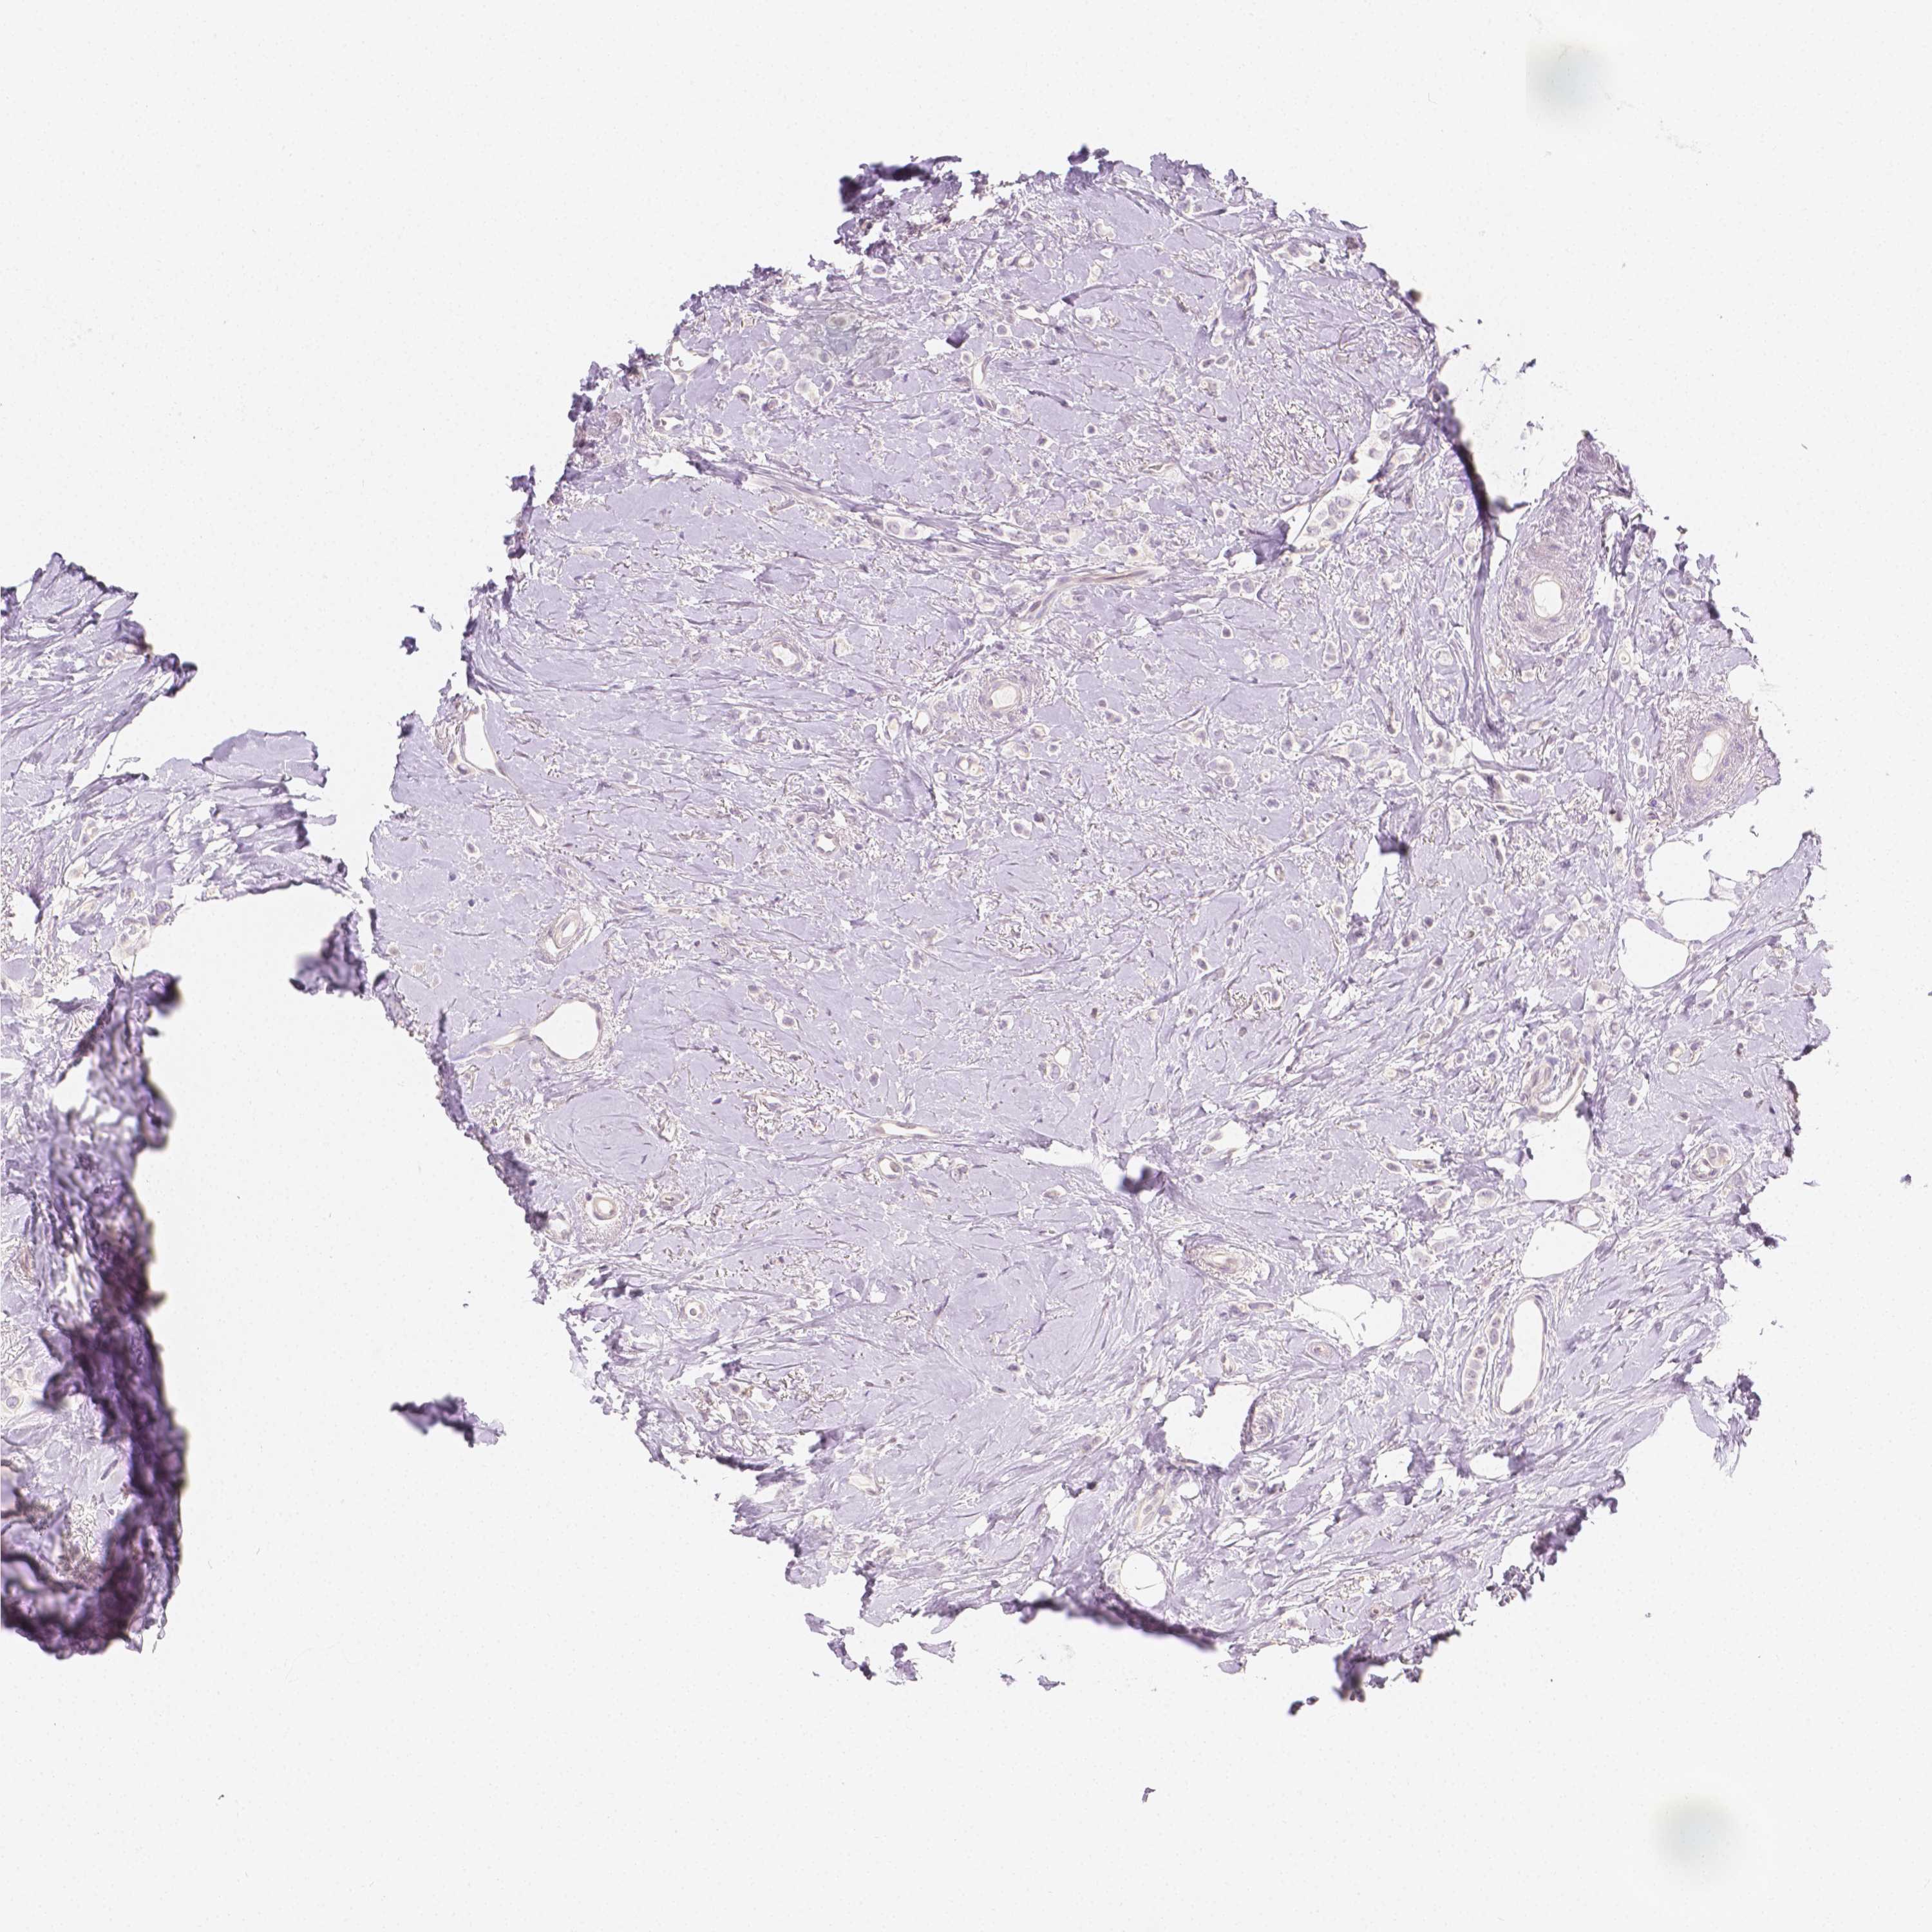

CANCER BREAST CANCER Show tissue menu

BRCA TCGA BRCA VALIDATION PROTEIN EXPRESSION

ANTIBODIES